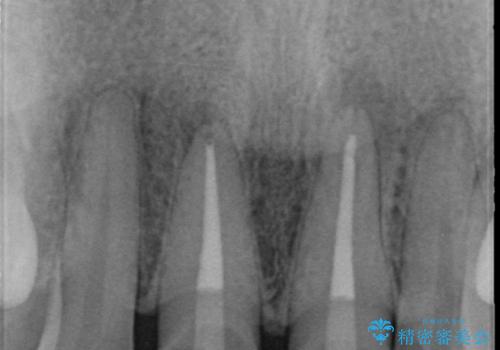

X線検査を行ったところ、共に深い虫歯が原因となり神経が死んでしまっている状態であることがわかり、根管治療を行ったのちセラミック補綴を行っていくこととなりました。

最終的なセラミッククラウンの精度・色調は非常に大事ですが、そこに至るまでの根管内環境の洗浄、ファイバーコアによる緊密な封鎖も長期的な予後に重要であると考えます。